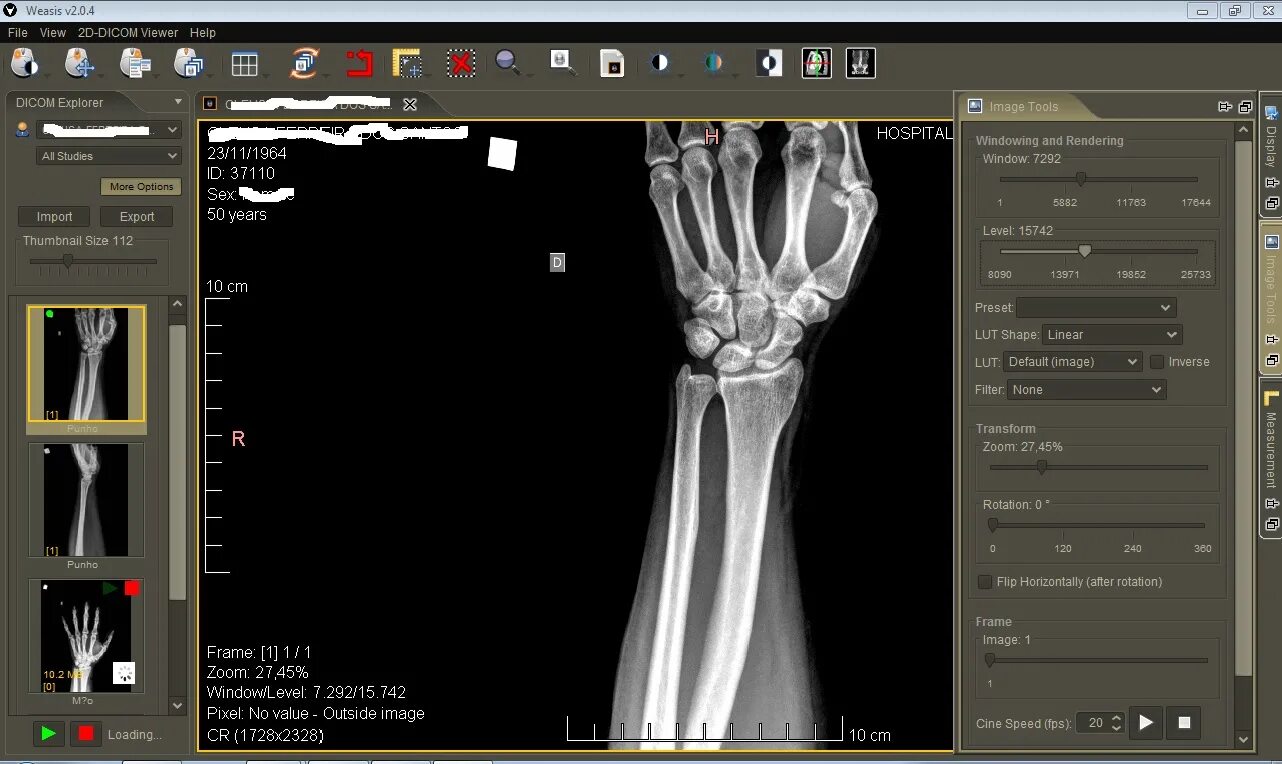

Радиант программа для кт